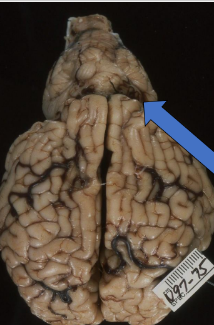

What is this in a calf?

Arnold-Chiari malformation